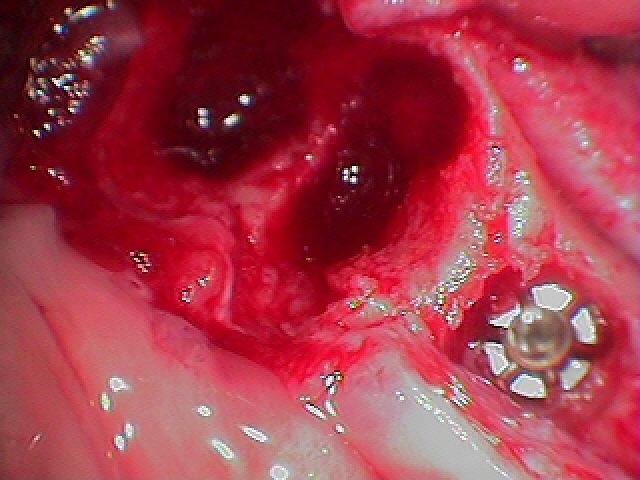

抜歯を行っています